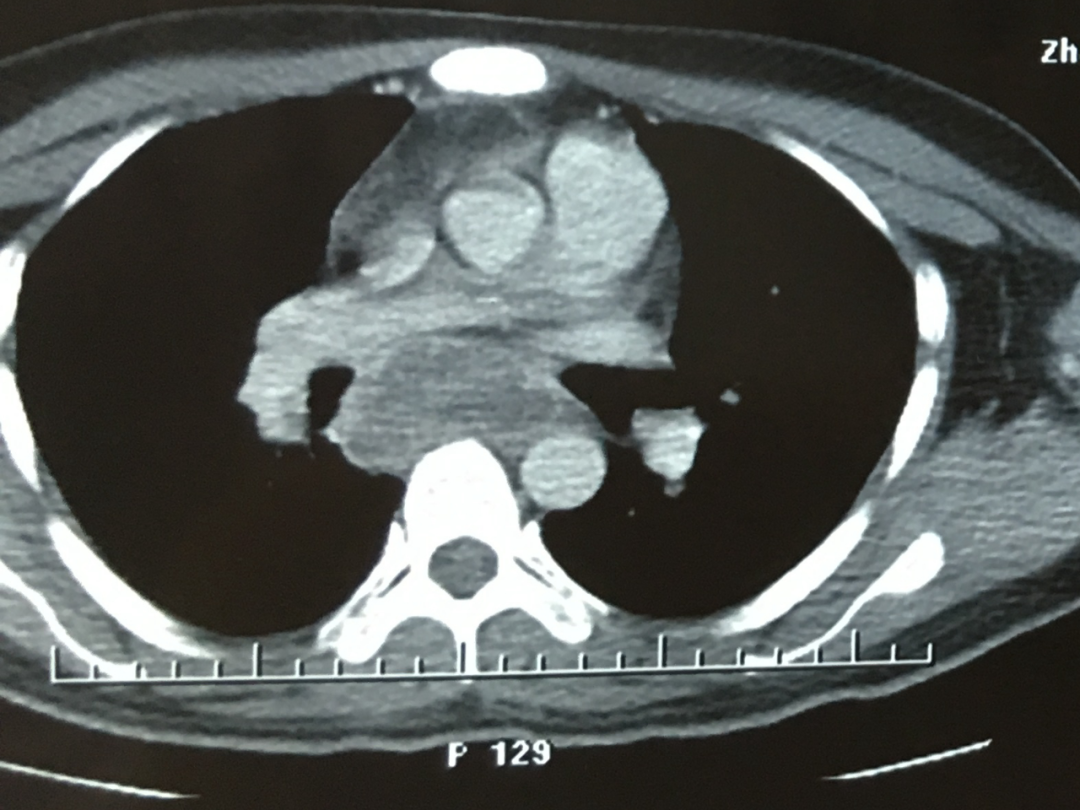

1. 原发性肺结核:主要表现为肺内原发病灶及胸内淋巴结肿大,或单纯的胸内淋巴结肿大。胸内淋巴结环形强化为胸内淋巴结结核相对特征性影像学表现。胸部 CT 可发现纵隔淋巴结肿大,但需与肿瘤淋巴结转移、淋巴瘤、结节病等相鉴别。

*原发性肺结核(胸内淋巴结结核):纵隔淋巴结肿大,增强环形强化为其特征。

*淋巴瘤:纵隔淋巴结肿大(「见缝插针」特征)

*肺结节病:纵隔及双肺门对称性淋巴结肿大,均匀强化